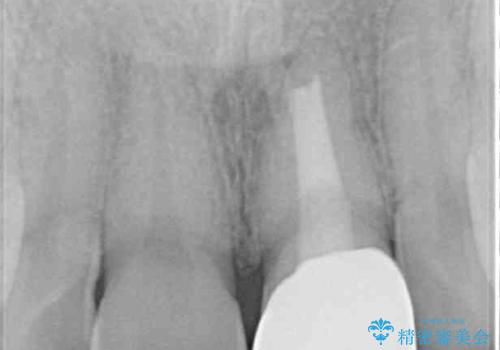

レントゲン写真より、歯の中の神経組織が失活していることが分かったため、根管治療、ファイバーコアによる土台築製を行い、オーダーメイドタイプのオールセラミッククラウンにて補綴することとしました。